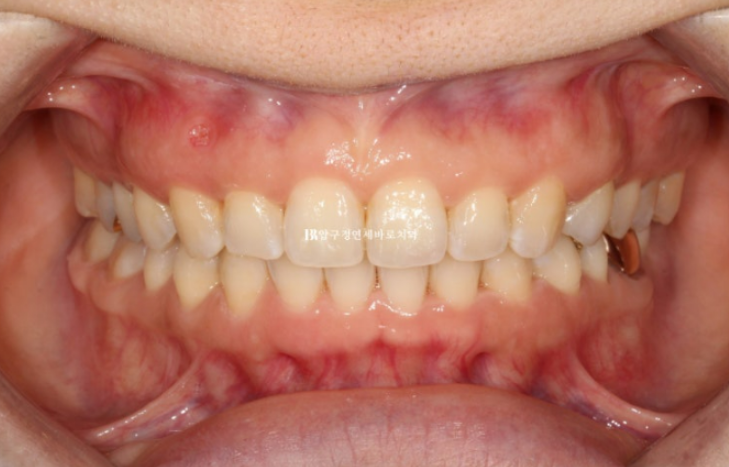

24년 1월 교정치료를 위해 내원하신 분입니다.

예전에 브라켓 철사 교정치료를 이미 했고 여러가지 불편한 점을 고치기 위한 재교정입니다.

교합평면이 기울어져 있습니다.

이렇게 평면이 기울어져 있으면 앞니도 그에 맞춰 기울어져 있는 경우가 많습니다.

윗니가 아랫니를 많이 덮어 아랫니가 전혀 보이지 않을 정도의 심한 과개교합 입니다.